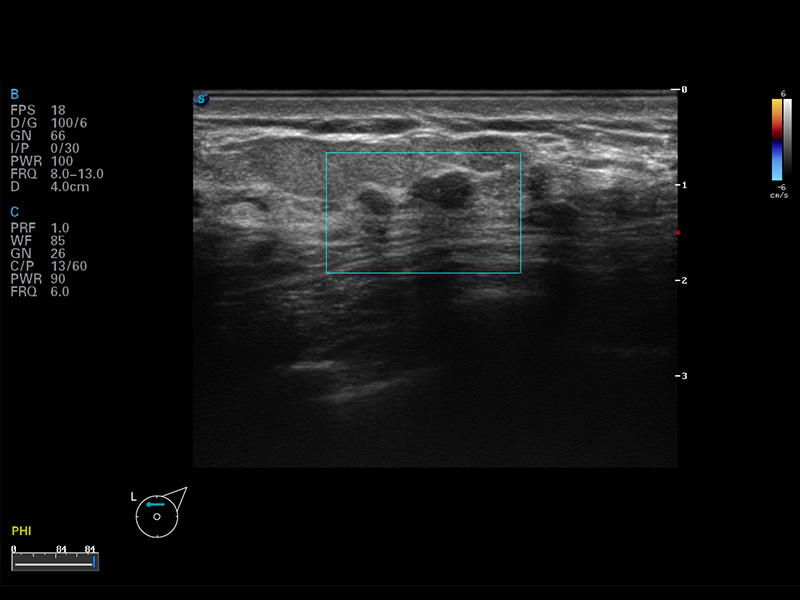

S8 EXP便攜式彩色多普勒超聲診斷儀是開立醫(yī)療研發(fā)的高端全身應(yīng)用型便攜彩超。高通道的VIS平臺(tái)融合可視化(Visual)、智能化(Intelligent)和人性化(Smart)的特點(diǎn),配以開立醫(yī)療自主研發(fā)生產(chǎn)的探頭大家族,使您能夠快速、準(zhǔn)確的獲得病人信息,提高工作效率的同時(shí)減輕疲勞。

成像技術(shù)

空間復(fù)合成像